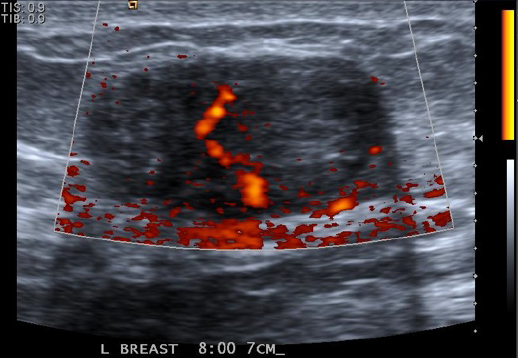

• *Heterogeneous ill-defined region**

• Echogenic inflammatory fat

• Hypoechoic glandular parenchyma

• Dilated ducts

Hypervascular

Skin thickening

Reactive axillary lymph node

• *Retroareolar abscess** (complicated)

• Hypoechoic heterogeneous fluid collection

• Mobile debris

• Irregular margins

• Posterior enhancement

• Hypervascular walls (avascular within)